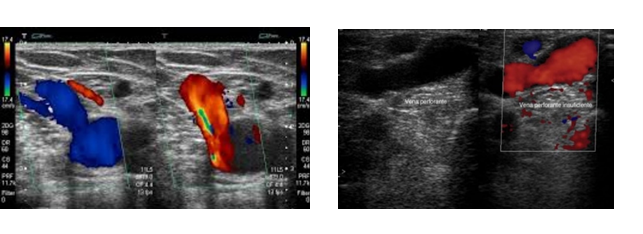

Paciente femenina de 33 años de edad, mestiza, reside en la ciudad de Riobamba en Ecuador, quien declaró no consumir alcohol o tabaco, no refiere antecedentes patológicos, así como quirúrgicos de importancia. Acude a consulta de cirugía vascular por aumento de volumen del miembro inferior derecho, que se acompaña de una mancha violácea en gran parte de su extremidad derecha, según refiere, además de sensación de pesadez, dolor y hormigueo ipsilateral. Al examen físico signos vitales dentro de parámetros normales. En cuanto al estado general: paciente consciente orientada en tiempo, espacio y persona, afebril, hidratada. Al examen físico regional, se evidencia nevus hiperpigmentario en cara lateral de pierna, muslo, y glúteo derecho además de várices de localización atípica en toda la cara lateral de pierna y muslo ipsilateral (Figura 2 A y C). Se realiza ecografía Doppler y se le detecta una Insuficiencia de Safena Mayor (Figura 1 A y B). Además, se practica mensuración de la extremidad derecha e izquierda y se aprecia un aumento longitudinal de 3 cm en miembro inferior derecho en relación con el contralateral (Figura 2 B). Se diagnostica síndrome de Klippel-Trenaunay, que se caracteriza por la triada clásica presente en la paciente: nevus hiperpigmentario, hipertrofia ósea y de tejidos blandos en miembro inferior derecho además de varices atípicas. Para su manejo se le practica safenectomía mayor derecha, además se le envía zapato corrector de deformidad, en cuanto al nevus hiperpigmentario se le refirió a dermatología para tratamiento láser. En cuanto a la evolución, la paciente mejora los síntomas que motivaron su consulta fundamentalmente el cansancio, dolor y parestesias en el miembro inferior afectado.

Se realiza exploración ecográfica con transductor lineal apreciándose unión safeno femoral dilatada e incompetente de 8 mm de diámetro, vena safena mayor dilatada e incompetente con reflujo de 20 segundos en todo su trayecto. B. En cara lateral de muslo se aprecian venas perforantes de 6 mm de diámetro a 5 cm suprageniculares con arco anterior de 5 mm incompetente.